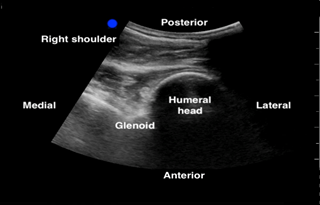

An anterior shoulder dislocation will show the humeral head displaced to the far field region of the screen, while the posterior dislocation will show the humeral head displaced to the near field region (Figures 3 and 4). A shoulder subluxation will show the humeral head partially sliding (or “dislocating”) in and out of the GHJ with shoulder movement (Figure 5). While less accurate, POCUS can also help identify fractures, such as the Hill-Sachs, the Bankart, or a humeral head fracture (Figure 6).

Figure 2: Right shoulder anterior dislocation